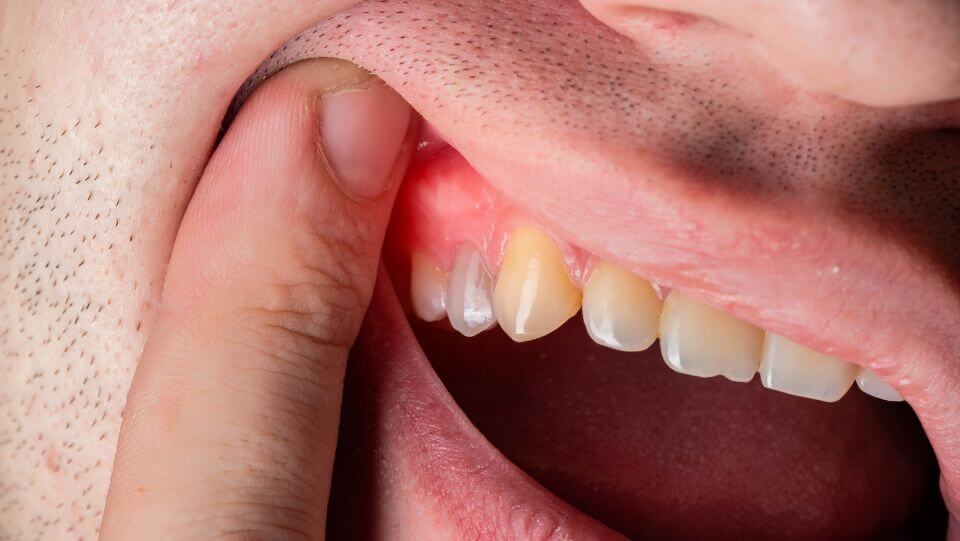

Characterized by symptoms such as red, swollen, and receding gums, loose teeth, and persistent bad breath, periodontal disease can be a silent yet potent threat to your health.

Symptoms include red, swollen, and tender gums that bleed easily (especially during brushing and flossing), persistent bad breath, receding gums, and loose teeth. If you notice any of these symptoms, it is essential to seek professional dental care promptly.